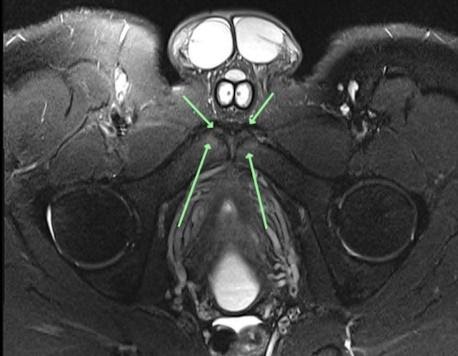

Here is an example of this in a late teenage footballer. Central pubic and lower abdominal pain radiating into bilateral medial groin adductor region. The axial oblique MRI images (figure 3 and 4) show pubic apophysitis with oedema and mild fragmentation of apophyses. It is an unusual diagnosis but worth bearing in mind in younger patients playing multi-directional demand sports with adductor or pubic related groin pain.

Figure 3

Figure 4